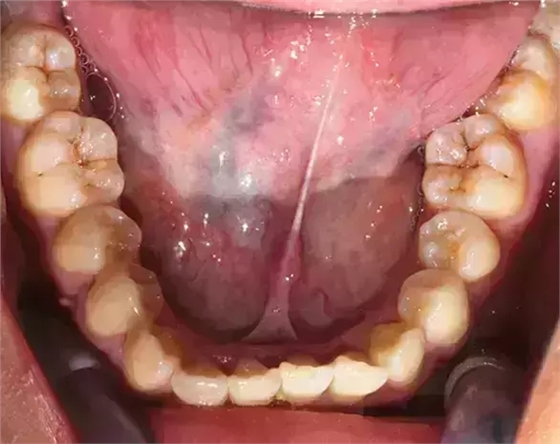

上下牙列擁擠,磨牙尖牙Ⅱ 類關(guān)系,3 度的深覆牙合,上頜中切牙伸長內(nèi)傾拔除上頜雙側(cè)的第一前磨牙,先粘上頜高轉(zhuǎn)矩的自鎖托槽排齊牙列,唇向開展上頜切牙,有一定的覆蓋,粘下頜標準轉(zhuǎn)矩托槽,上頜 1, 2 之間植入種植支抗壓入,同時后牙 5, 6 之間植入種植支抗內(nèi)收前牙,打開咬合關(guān)閉間隙。治療關(guān)鍵:前牙轉(zhuǎn)矩的控制第 1 個月 上頜粘上 Damon Q 高轉(zhuǎn)矩托槽,上 .014 熱激活 NiTi 絲。第 3 個月 上換 .014 x .025 熱激活 NiTi 絲。第 5 個月 上頜基本排齊,覆蓋增大,上換 .017 x .025 NiTi絲,下頜粘托槽,下 .014 熱激活 NiTi 絲。第 7 個月 上 .017 x .025 NiTi 絲加搖椅,下?lián)Q .014 x .025 熱激活 NiTi 絲第 9 個月 上頜換 .019 x .025 NiTi 絲加搖椅,下頜換 .017 x .025 NiTi 絲第 11 個月 下頜換 .019 x .025 加搖椅,上頜 1, 2 之間, 5, 6 之間植入種植釘,下頜出現(xiàn)散隙。第 13 個月 上頜換 .019 x .025ss 加搖椅,前牙種植釘用 Power Chain 壓低前牙(每側(cè) 100g),后牙種植釘關(guān)閉間隙(每側(cè) 150g),下?lián)Q .019 x .025ss,Power Chain 關(guān)閉間隙。第 19 個月 上頜前牙基本壓低到位去除前牙種植釘,繼續(xù)用關(guān)閉間隙,下頜散隙關(guān)閉。

第 22 個月 上頜覆蓋變小,去除 5, 6 之間種植釘,后牙前移關(guān)閉間隙。第 30 個月 患者未配合中線牽引,下中線仍有 1mm 右偏,患者對矯治效果滿意要求拆除,拆除固定矯治器,取模制作壓模保持器。 1.骨性 Ⅱ 類的患者內(nèi)收前牙時需對上頜前牙的轉(zhuǎn)矩進行較好的控制才能獲得良好的面型和唇部形態(tài)。 2.露齦笑的患者治療前要分析其病因是唇、牙齦、牙齒、牙槽骨、上頜骨或多種因素結(jié)合,再制定矯治方案。 3.Ⅱ 類第二分類伴露齦笑的患者的上頜前牙移動軌跡是唇向開展-壓低-整體內(nèi)收。 4.Ⅱ 類第二分類牙齒舌傾比較厲害的情況,上頜中切牙慎用樹脂咬合墊。 5.壓低前牙或控根移動時容易發(fā)生牙根的吸收,需輕力緩慢的移動。